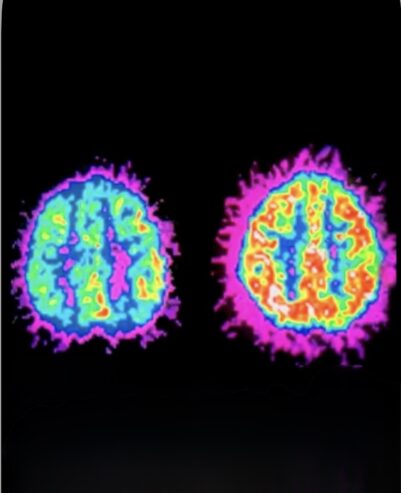

ADHD brains are literally smaller and have broken dopamine systems that cause addiction

Brain scans show that people with ADHD often have differences in the prefrontal cortex — the area of the brain responsible for focus, planning, and decision-making.

Studies have also found that brain regions involved in reward processing, such as the striatum, can be smaller in some individuals with ADHD.